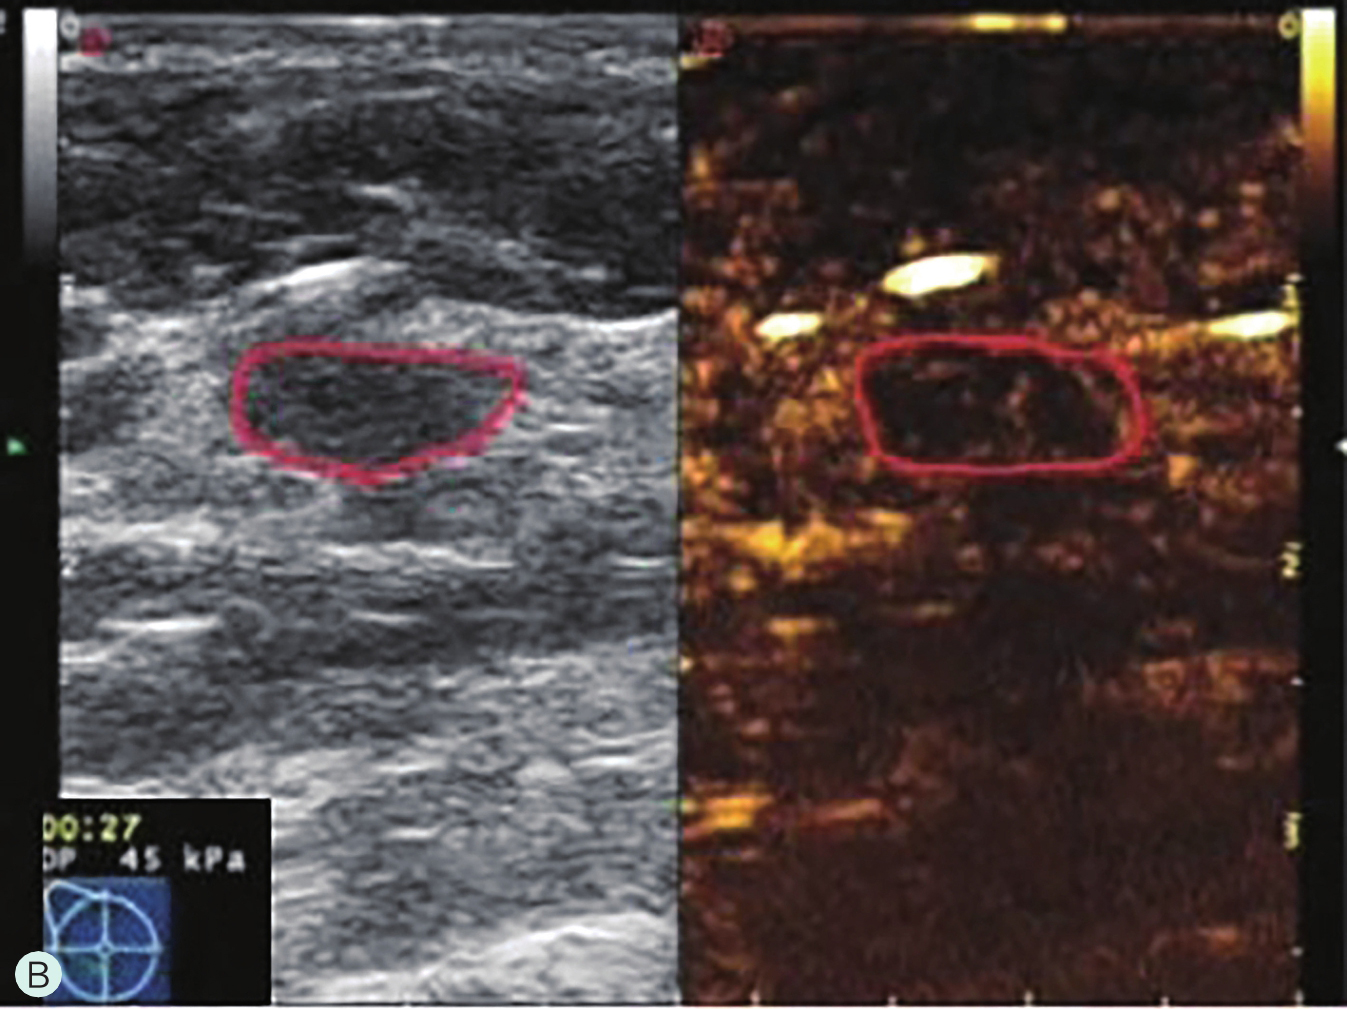

图2-2-11 乳腺肿瘤的微血管演进示意图

6.定量分析时,对不同区域分别取样,或包络整个病灶取样,所获得的时间-强度曲线参数也会出现差异,故取样时应尽可能包络病灶最大范围,并在病灶内及正常腺体以相同的感兴趣区面积多点取样进行相互比较,取样时应避开首先增强的滋养血管或无增强区,定量分析作为定性分析的辅助工具,应基于定性分析判读结果综合分析。